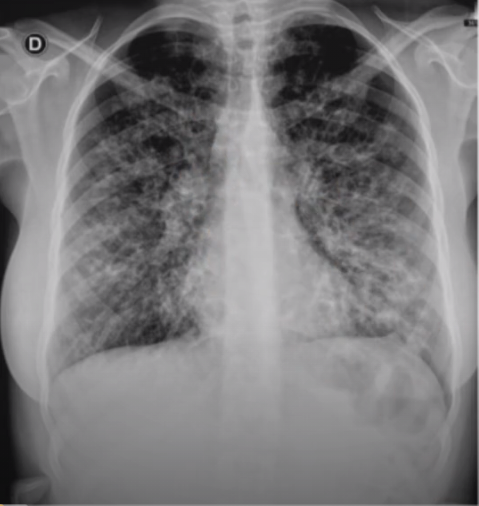

raio x de tórax fibrose cística:

Bronquiectasias em ápices

espessamento brônquico

atelectasias